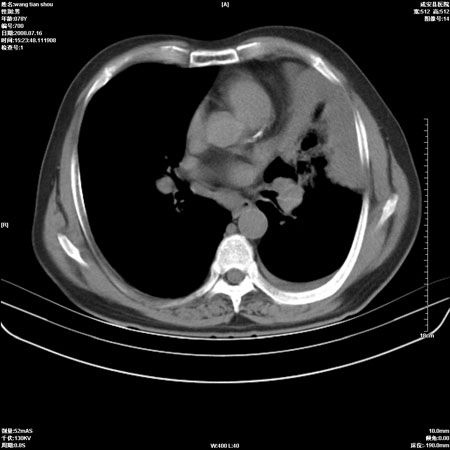

以下是引用qingjing在2008-7-16 19:55:00的发言:[br]1、左上肺不张并堵塞性炎症,建议支气管镜详查;[br]2、左侧胸腔少量积液。

以下是引用wzr在2008-7-16 20:26:00的发言:[br]左肺肺不张伴阻塞性肺炎!另:左侧胸腔少量积液。建议纤支镜检查!